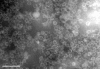

Human bocavirus (HBoV) is a widespread respiratory virus. To improve diagnostic methods, we conducted immunoglobulin (Ig) G and IgM enzyme immunoassays with recombinant virus-like particles of HBoV as antigen. Acute-phase and follow-up serum samples from 258 wheezing children and single serum samples from 115 healthy adults in Finland were examined. Our assays had a sensitivity of 97% and a specificity of 99.5%. Of adults, 96% had immunity; none had an acute infection. Of 48 children with serologically diagnosed acute HBoV infections, 45 were viremic and 35 had virus in nasopharyngeal aspirates (NPAs). Of 39 HBoV NPA PCR-positive children co-infected with another virus, 64% had a serologically verified HBoV infection. HBoV caused illness of longer duration than rhinovirus and of equal severity to that of respiratory syncytial virus. Among children with bronchiolitis, >25% had acute HBoV infections. Accurate HBoV diagnosis requires serologic analysis or PCR of serum; PCR of NPAs alone is insufficient.